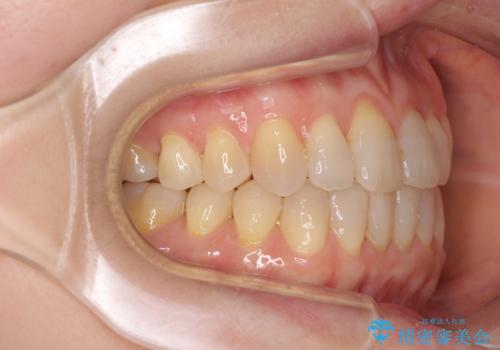

前歯の叢生と切端咬合 インビザラインによる矯正治療

- 前歯のデコボコを気にして来院された患者様です。

上下前歯の先端同士が接触する切端咬合であったため、上顎は歯列を拡大し、下顎はIPR(歯と歯の間を削る)により叢生を解消しながら歯列を小さくすることとしました。

治療前から歯肉退縮が認められ、矯正治療により悪化する可能性が考えられたため、無理のない歯の移動と頻繁な経過観察を行いました。

切端咬合はスムーズに解消され、前歯の負担を軽減させることができました。